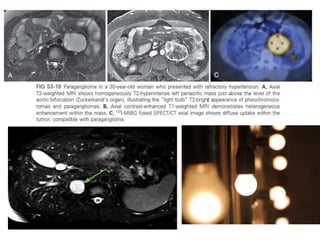

PHAEOCHROMOCYTOMA

• Commonest tumor of adrenal medulla

• Paragangliomas arising from neural crest cells

• Follow “RULE of 10”

 ~10% are extra-adrenal

 ~10% are bilateral

 ~10% are malignant

 ~10% are found in children

 ~10% are familial (MEN II A/B,VHL)

 ~10% are not associated with hypertension (non functioning)

 ~10% contain calcification

• Diagnosis :

clinical: young patient with HTN, paroxysmal hypertension, headaches,

visual blurring, sweating and vasomotor changes

Biochemical : plasma and urinary levels of catecholamine , vanillylmandelic

acid (VMA) and metanephrines .

• Imaging studies are performed to localise the tumor and to aid surgical

planning for resection

• Pheochromocytomas are nicknamed "imaging chameleons" because many

imaging features overlap with other tumors. Mimicks typically with

necrotic adrenal metastasis and about 30% with adenomas

• MRI is better for detecting extraadrenal pheochromocytoma and

recurrence after surgery.

• So called classic "light bulb sign", which is homogeneous high signal

intensity on T2W-images is seen in 65% of cases